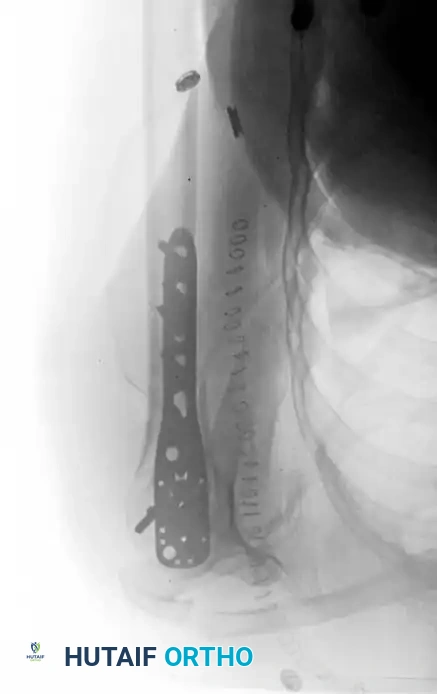

Open Reduction and Internal Fixation (Locked Plating)

For complex three- and four-part fractures, particularly in patients with osteoporotic bone, proximal humeral locking plates have revolutionized treatment. These fixed-angle constructs provide superior biomechanical stability compared to conventional non-locking plates.

Surgical Approach:

* The deltopectoral approach is the workhorse for proximal humeral ORIF, utilizing the internervous plane between the deltoid (axillary nerve) and pectoralis major (medial/lateral pectoral nerves).

* The cephalic vein is identified and typically retracted laterally with the deltoid to protect its tributaries.

Fixation Principles:

* Anatomic reduction of the medial calcar hinge is critical to prevent varus collapse.

* Heavy nonabsorbable sutures are passed through the rotator cuff tendons and tied to the plate to neutralize tuberosity pull.

* Locking screws are placed into the humeral head, ensuring they do not penetrate the articular surface (subchondral placement is ideal).